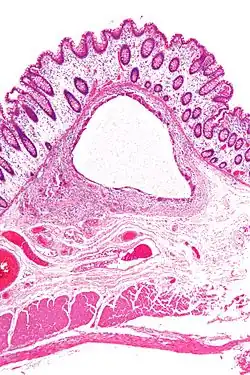

Lung cysts

A lung cyst, or pulmonary cyst, encloses a small volume of air, and has a wall thickness of up to 4 mm.[3] A minimum wall thickness of 1 mm has been suggested,[3] but thin-walled pockets may be included in the definition as well.[4] Pulmonary cysts are not associated with either smoking or emphysema.[5]

A lung cavity has a wall thickness of more than 4 mm.[3]